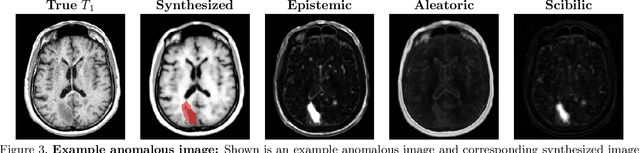

Abstract:Medical images are often used to detect and characterize pathology and disease; however, automatically identifying and segmenting pathology in medical images is challenging because the appearance of pathology across diseases varies widely. To address this challenge, we propose a Bayesian deep learning method that learns to translate healthy computed tomography images to magnetic resonance images and simultaneously calculates voxel-wise uncertainty. Since high uncertainty occurs in pathological regions of the image, this uncertainty can be used for unsupervised anomaly segmentation. We show encouraging experimental results on an unsupervised anomaly segmentation task by combining two types of uncertainty into a novel quantity we call scibilic uncertainty.